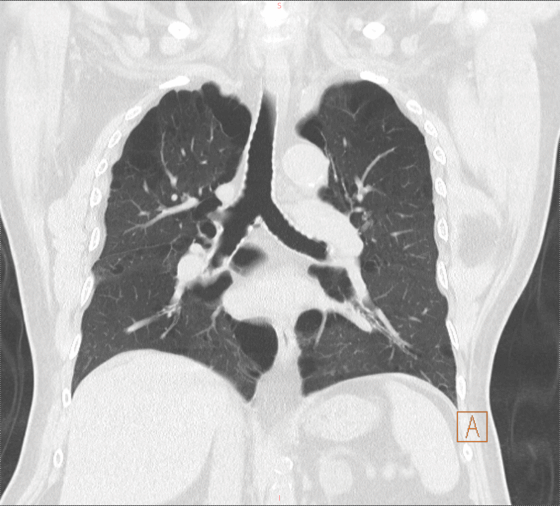

老王是个老烟民,40多年的烟龄,每天1-2包烟,一直没有间断。双肺满布大疱,肺气肿明显,肺功能结果非常差。并且老王缺乏锻炼,身形肥胖,170cm的身高,体重达到90kg,对肥胖患者而言,相对肺容积较小,这使本身就差的肺功能更显得捉襟见肘。

右图:术前CT影像(双肺肺气肿、肺大疱)